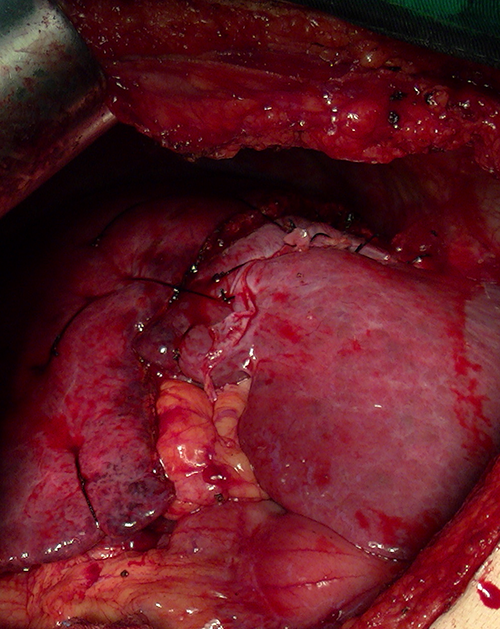

S8肝癌---改良肝中叶切除(3D打印)